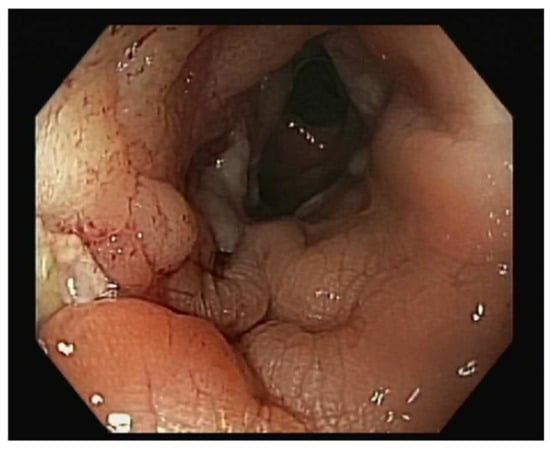

The treatment approach was discussed in a multidisciplinary team with the involvement of Gynaecology, Gastroenterology, General Surgery, Pathology, and Radiology. The patient underwent a programmed exploratory laparotomy via a midline incision which identified the sigmoid wall adherent to the uterine fundus with an approximately 3 cm extension; the uterus was normal in size and consistent with the small myomas identified; the adnexa were atrophic; and there were no adhesions or other abnormal findings. The procedure continued with en bloc colonic resection and primary anastomosis in the same operative time, total hysterectomy, and bilateral adnexectomy. Intraoperative frozen section examination revealed fibrous and unspecific inflammatory tissue without malignant aspects and, therefore, the procedure was finalized (Figure 3 and Figure 4).

Figure 4. A close look at the sigmoid colon adherent to the serosal surface of the uterine fundus with a fistulous communication between the two viscera.